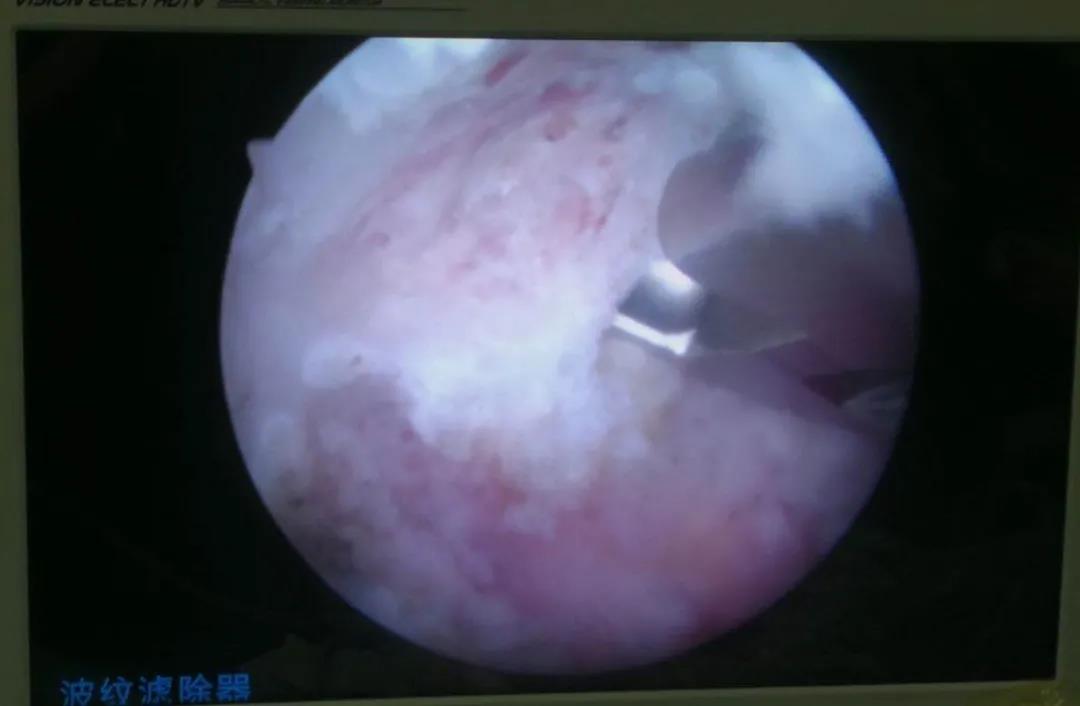

鏡下動(dòng)力磨削椎板

椎板鉗清理椎板及黃韌帶